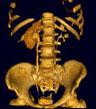

问题 女,64岁,反复尿频尿急尿痛6年余,尿常规检查:红细胞(++),白细胞(++)CT扫描如图示,下列说法正确的是 ( )

选项 A、考虑为慢性输尿管炎 B、考虑为输尿管移行细胞癌 C、右肾积水 D、右侧输尿管上段扩张 E、右侧输尿管下段管壁增厚,管腔狭窄

答案 ACDE